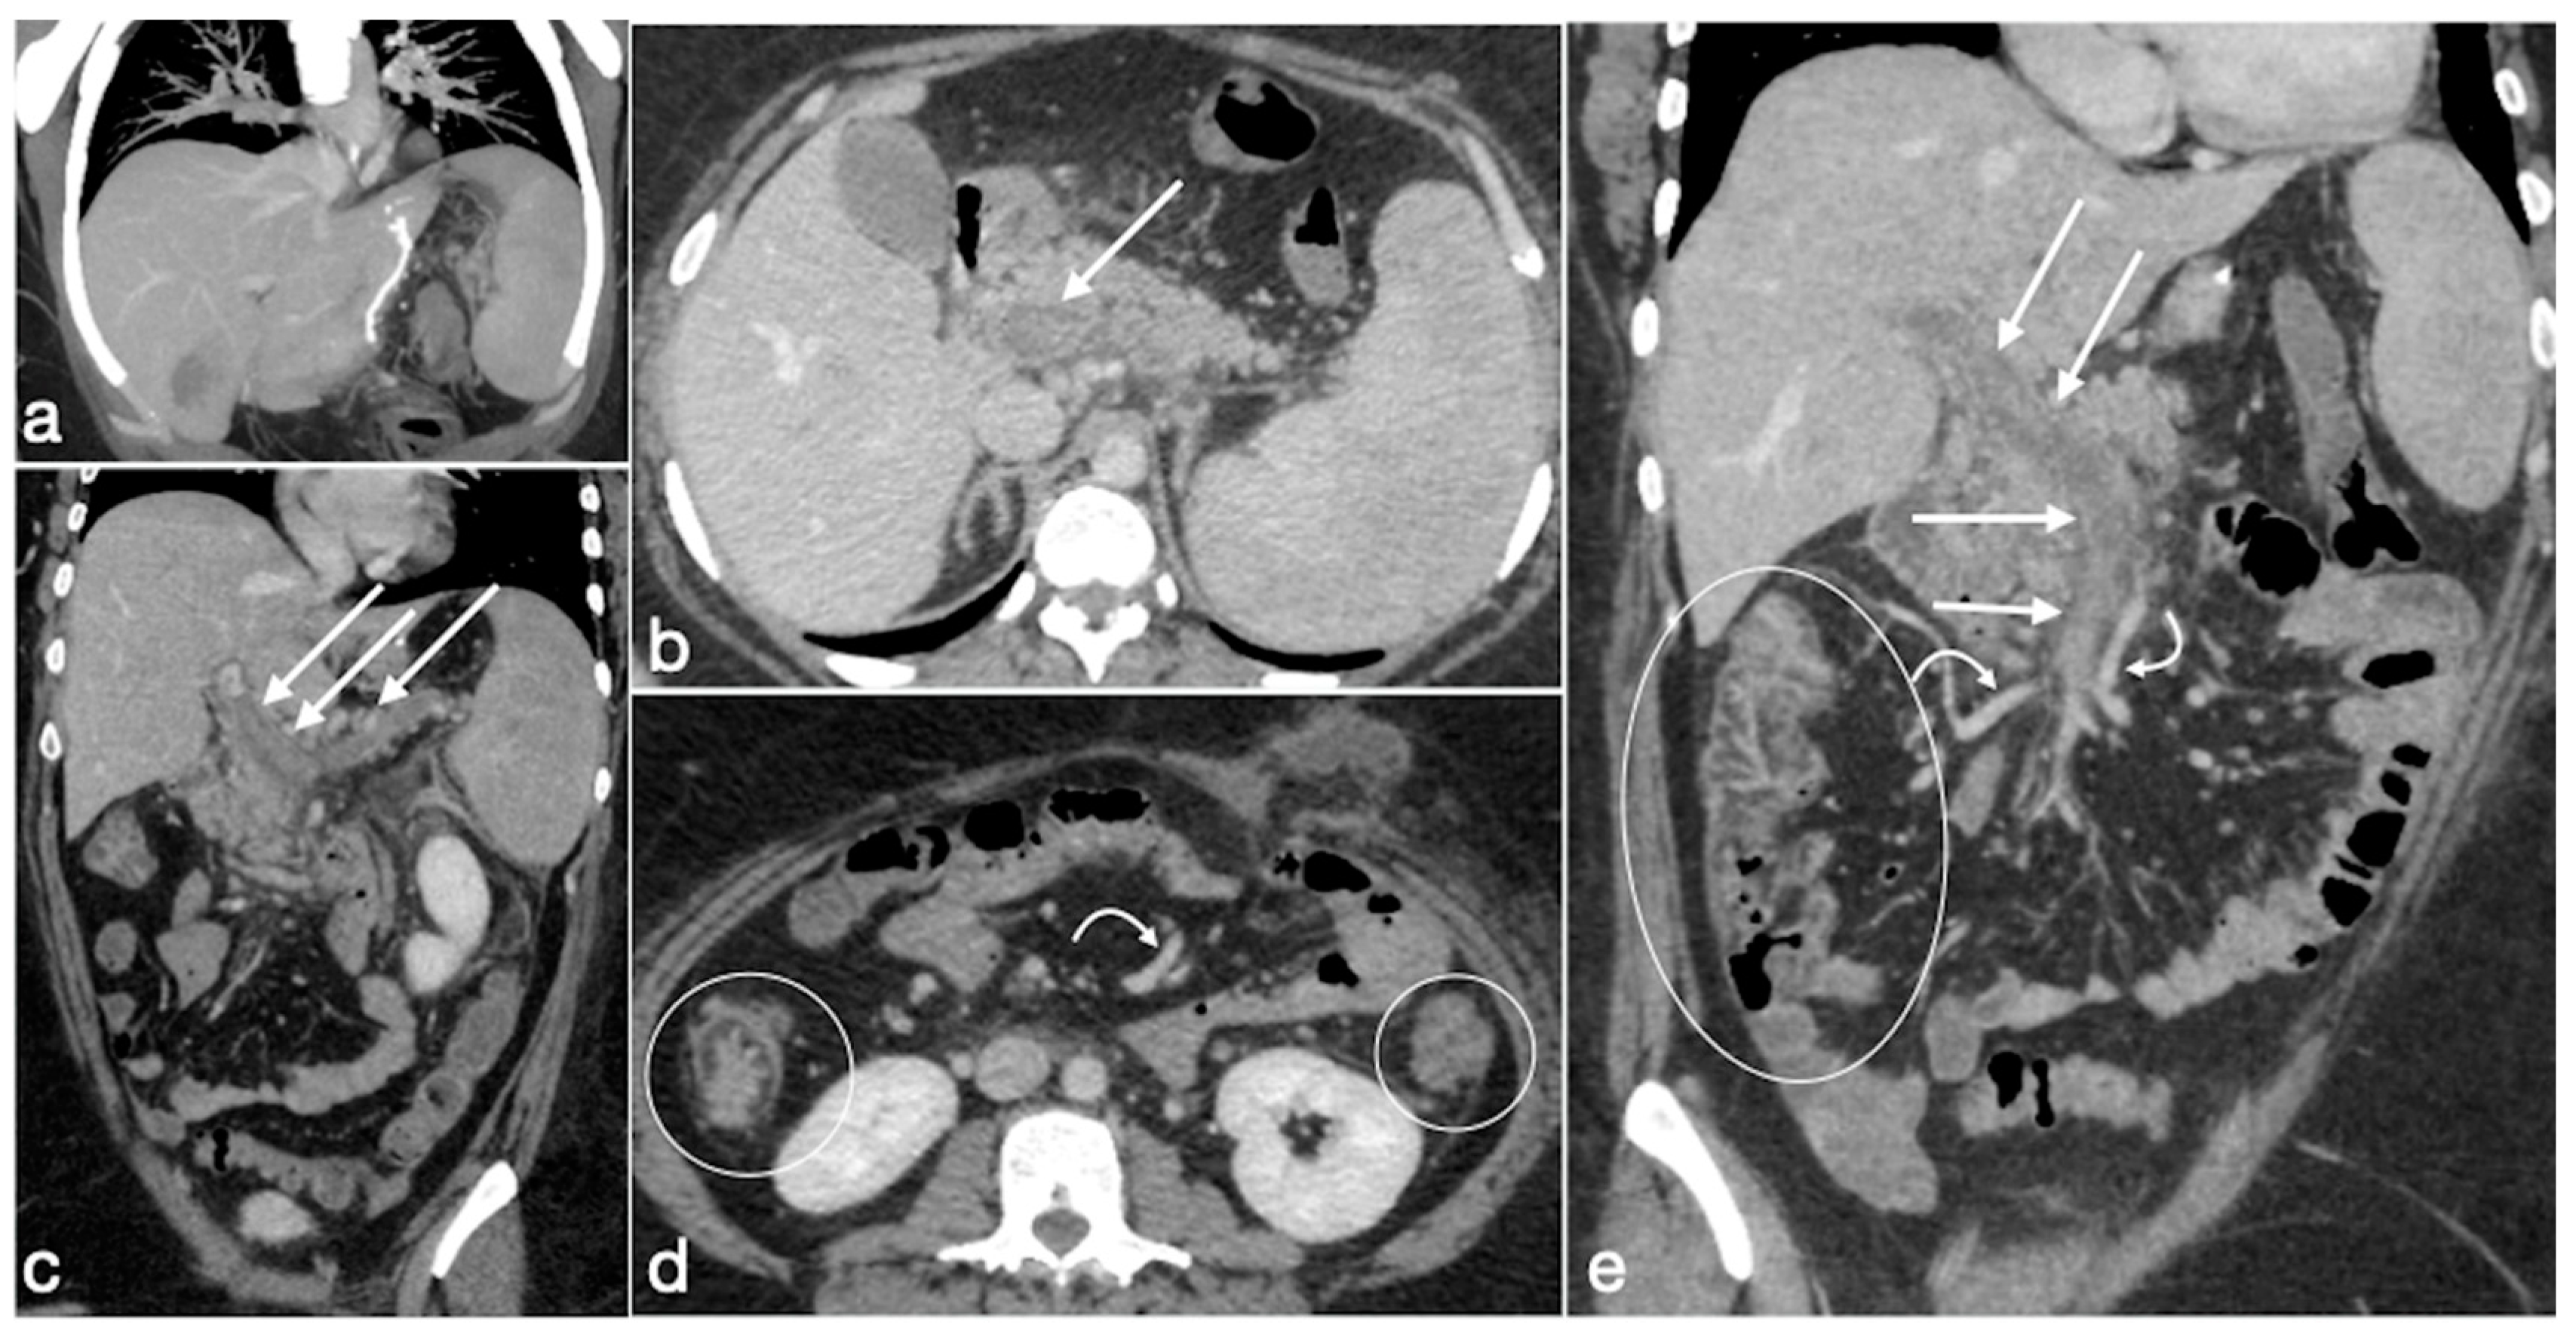

Figure 19. Patient 1. Porto-spleno-mesenteric venous thrombosis and colonic ischemia after sleeve gastrectomy. A 37-year-old female patient underwent sleeve gastrectomy. The patient came to the emergency department complaining of abdominal pain and fever. See the surgical gastric suture (a, coronal oblique view), the enlarged and thrombosed spleno-portal lumen (b, axial view; c, coronal oblique view, straight arrows), the consequential mesenteric congestion (d, axial view; e, coronal view, curved arrows), and the colonic ischemia (d, axial view; e, coronal view, circles). In the coronal view (e), the thrombosis that extends to the superior mesenteric vein lumen can be seen best. The patient was treated with multiple session of transhepatic catheter-directed thrombolysis.